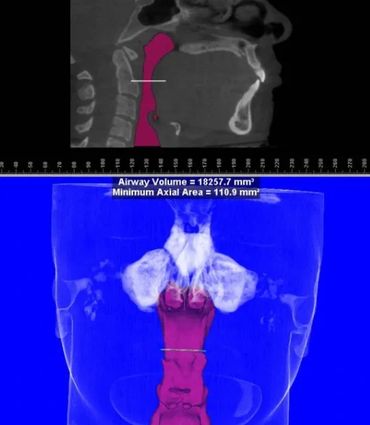

We also utilize the most prestigious Oral and Maxillofacial Radiologist in its field. Services offered for Radiographic Diagnostic Reporting include but not limited to: Implant Work-up, TMJ, Impaction/Localization study, Tissue Pathology, Airway and Sinus Evaluation.

This one scan provides more images than plain film conventional imaging, with complete visualization of the patient's entire maxillofacial region. These images clearly display TM disorders, impacted teeth, critical bone and tooth relationships, oral- nasal airways, para-nasal sinus, mandibular canal and difficult to see pathologies within one volume. The user friendly software system reconstructs true size, distortion free, high resolution images.